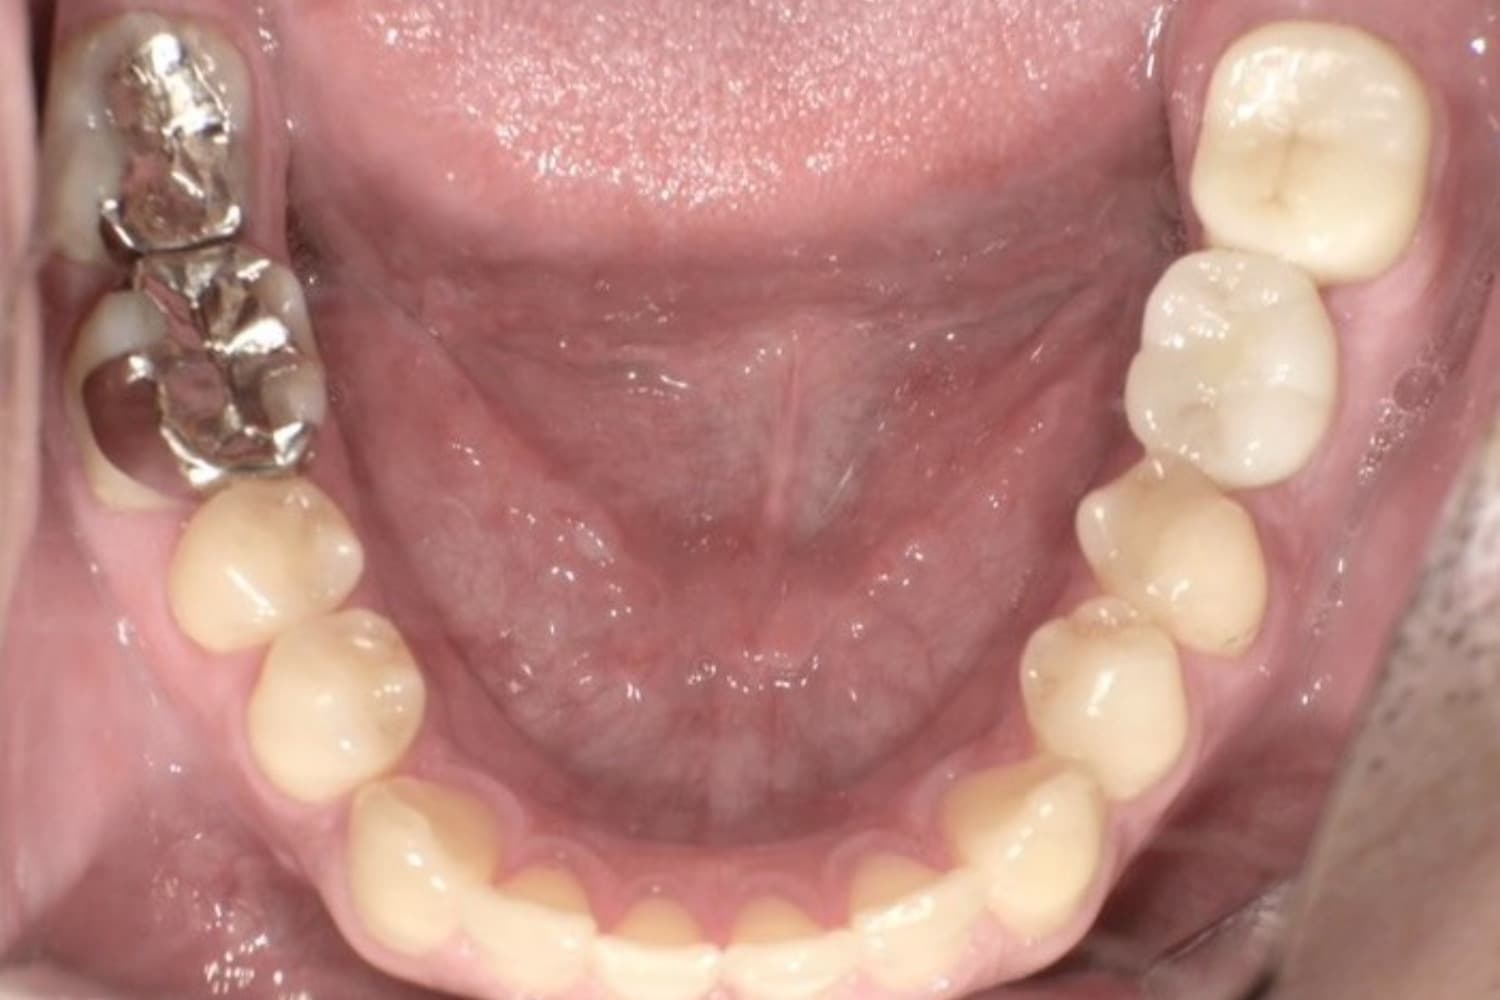

After

下顎全てをオールオン4で治療

50代

男性

入れ歯が合わなくて痛い。固定式のインプラントで美味しくご飯を食べられるようにして欲しい。

6ヶ月〜8ヶ月

8回

合計:220万円(税込み242万円) インプラント4本(インプラント本体) : 20万円×4本=80万円(税込み88万円) 上部構造::ジルコニアクラウン×12本=140万円(税込み154万円)

・手術後には腫れや痛みが生じる可能性があります。 ・インプラント診療は自由診療となります。 ・治療後、慣れるまでは一定期間噛むと違和感が生じることがあります。 ・歯磨きにコツが必要なので、歯磨きの練習が必要。